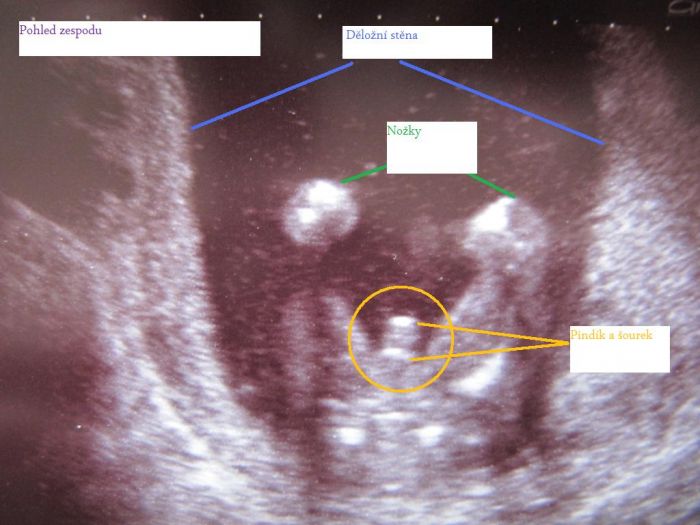

Tak se hlásím po dnešní genetice, zdá se být všechno v naprostém pořádku, tak jsem šťastná jak blecha, teď ještě v tom 20tt., ale věřím, že když dopadlo tohle dobře, tak i ten velký bude v pořádku. Je to definitivní kluk, pan profesor mi udělal i 3 fotky, jako dáreček (bez placení, na pohlaví jsem se neptala-sám se nabídnul, zda to chci vědět). Tak je připojuju, na jedné je z profilu s otevřenou pusinkou, na jedné zepředu-pěkně viditelná čočka v jednom oku a na poslední výbavička našeho frajera.

marse to je krasny:)akorat ta 3fotka na ty se moc nevyznam:)ja uz chci tajy vedet co mam v sobe za krasne mimi:(ale jdu az 14.:(nevydrzim to!:)

MeIDo, myslím, že druhému screeningu se říká Triple test. A ve 20.tt je velký ultrazvuk, ale nejsem si tím vůbec jistá. Junýsku, pro tebe (a ostatní, co si nejsou jisté) vkládám tu třetí fotku s vytvořeným popiskem

Snad jsem to pochopila správně a nepopletla to